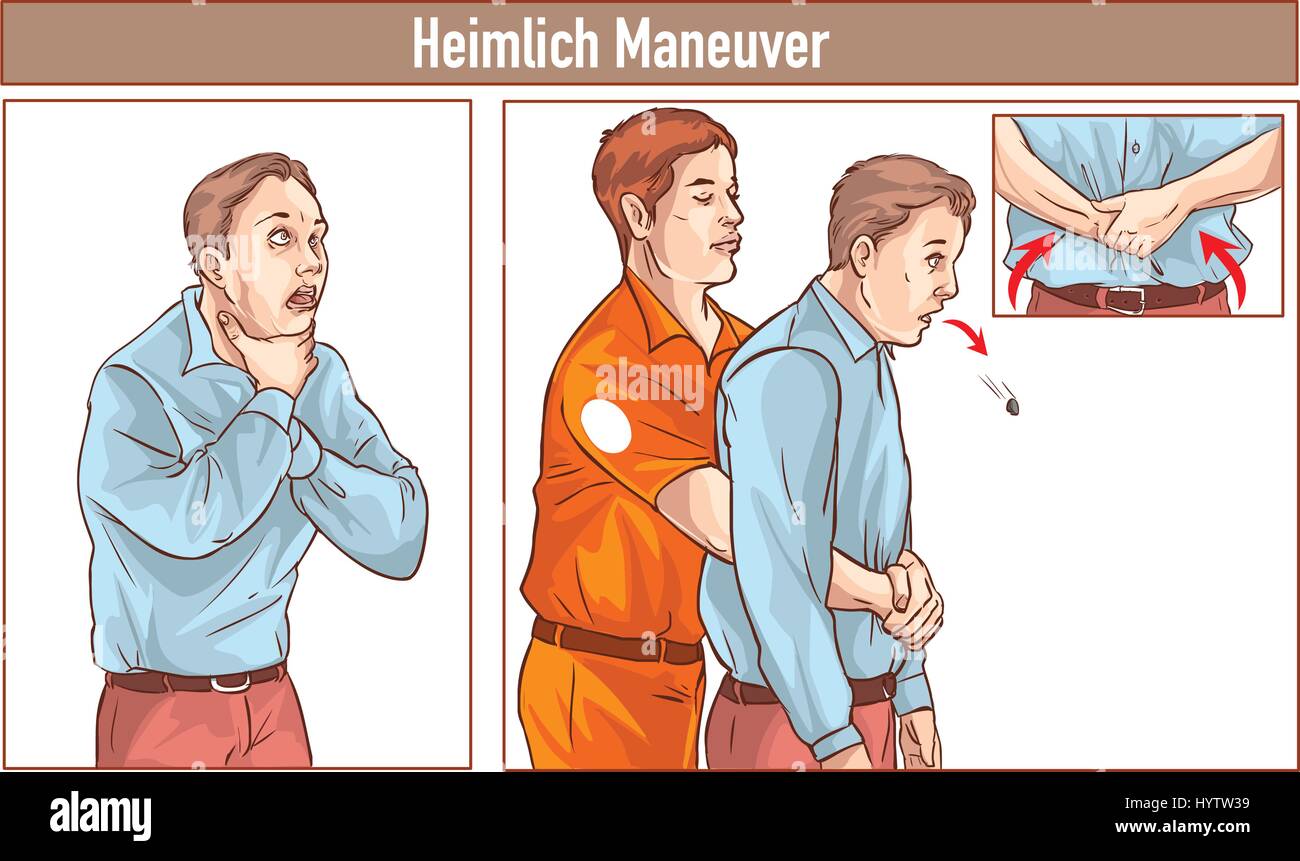

Clip Art of One man stands behind the conscious victim with his hands in the proper position on the victim's abdomen to perform the Heimlich maneuver Stock Vectorhttps://www.alamy.com/image-license-details/?v=1https://www.alamy.com/stock-photo-clip-art-of-one-man-stands-behind-the-conscious-victim-with-his-hands-137614829.html

Clip Art of One man stands behind the conscious victim with his hands in the proper position on the victim's abdomen to perform the Heimlich maneuver Stock Vectorhttps://www.alamy.com/image-license-details/?v=1https://www.alamy.com/stock-photo-clip-art-of-one-man-stands-behind-the-conscious-victim-with-his-hands-137614829.htmlRFHYTW39–Clip Art of One man stands behind the conscious victim with his hands in the proper position on the victim's abdomen to perform the Heimlich maneuver